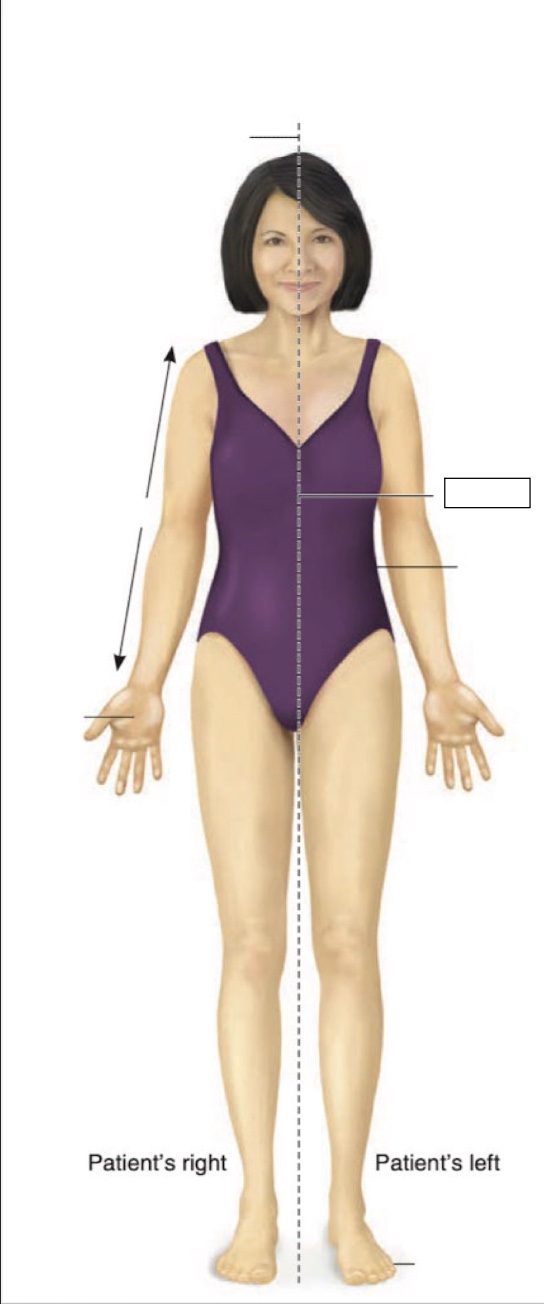

Posterior

Anterior

Superior

Inferior

Midline

Proximal

Distal

Palmar

Medial

Lateral

midsternal line

anterior axillary line

midclavicular line